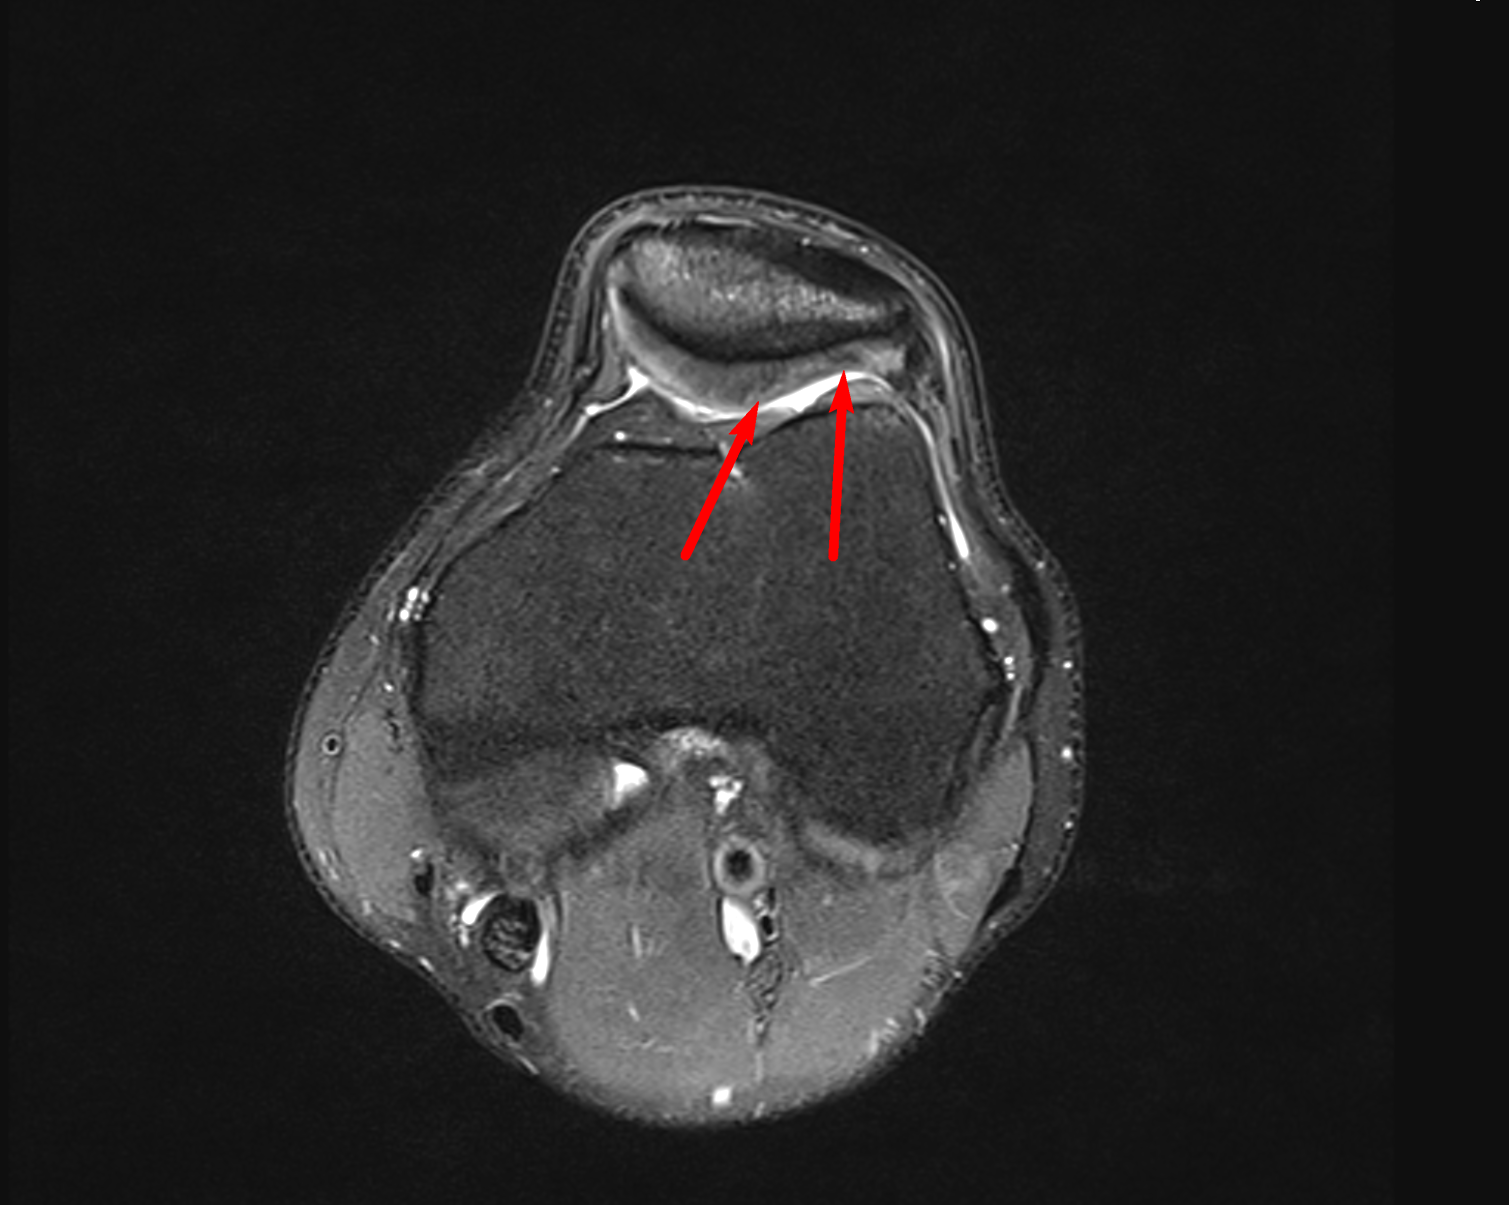

Ich bin´s mal wieder mit einem kleinen Zwischenstand. Mein Knie hat sich zum Zustand im Juni / Juli 2018 verbessert, ist aber noch anfällig bzw. schmerzempfindlich bei den falschen Bewegungen. Ich war nun beim 5. Arzt und das war erst der Zweite der sich die Bilder selbst angesehen hat. Alle anderen haben nur den Befund zu Rate gezogen. Der letzte Arzt meinte, der Schaden auf den Bildern ist maximal ein Knorpelschaden 2. Grades, wenn nicht sogar nur Grad 1. "Ihre Schmerzen können meiner Meinung nach nicht vom Knorpelschaden bzw. dessen Auswirkungen kommen".

Mein Physio ist unabhängig vom 5. Arzt auch schon länger der Meinung, dass meine Symptome eigentlich nicht auf einen klassischen Knorpelschaden hinweisen. Er vermutet ein ITBS (IT Band Syndrom).

Auf diese Auffälligkeit hat sich der 5. Arzt bezogen

Das hier habe ich entdeckt & wenn ich mich recht erinnere ist das auch das Bild, welches mir der Radiologe damals gezeigt hat,

Kann jemand anhand der Bilder eine Aussage treffen?